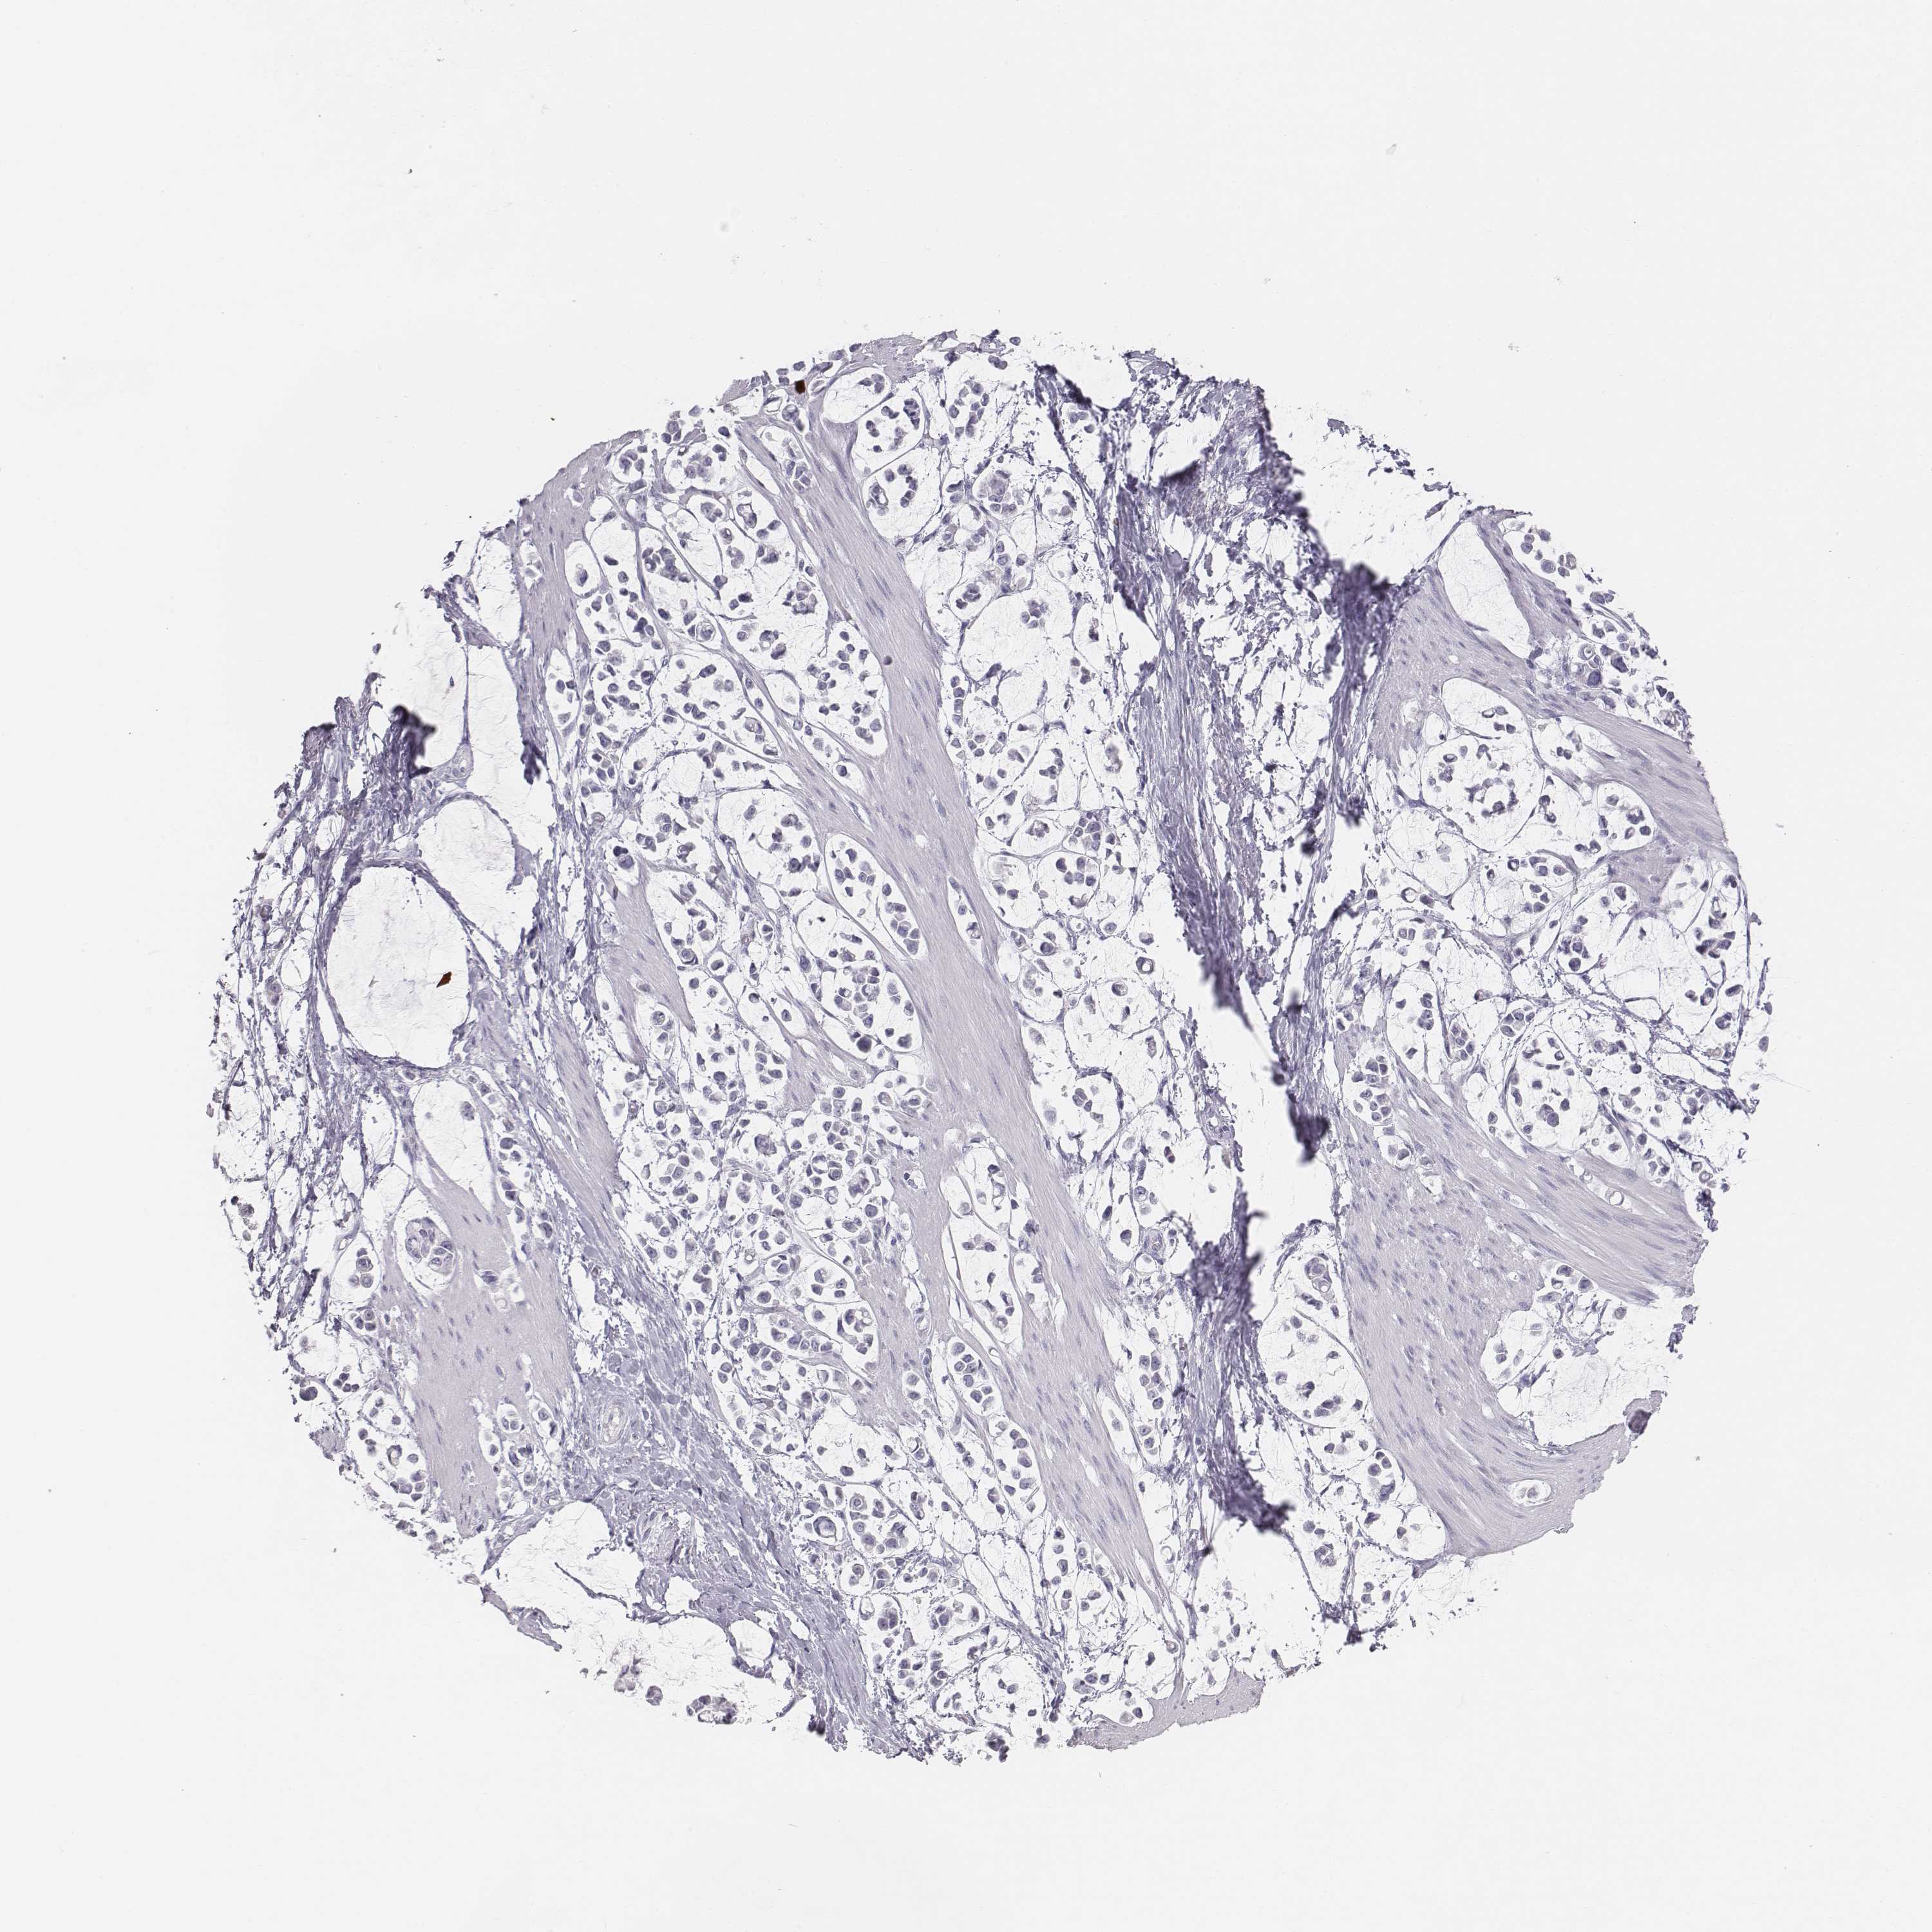

STOMACH CANCER - Protein expressioni

A mouse-over function shows sample information and annotation data. Click on an image to view it in a full screen mode. Samples can be filtered based on level of antibody staining by selecting one or several of the following categories: high, medium, low and not detected. The assay and annotation is described here.

Note that samples used for immunohistochemistry by the Human Protein Atlas do not correspond to samples in the TCGA dataset.

Antibody stainingi

Antibody staining in the annotated cell types in the current human tissue is reported as not detected, low, medium, or high, based on conventional immunohistochemistry profiling in selected tissues. This score is based on the combination of the staining intensity and fraction of stained cells.

Each image is clickable and will lead to virtual microscopy that enables deeper exploration of all samples and also displays staining intensity scores, fraction scores and subcellular localization as well as patient and tissue information for each sample.

Antibody HPA043261

Antibody HPA043264

Antibody HPA044028

Adenocarcinoma, NOS